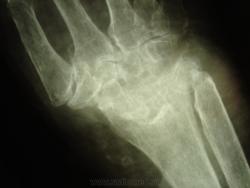

женщина,1930 г.р. , в наравлении -деформирующий артроз? В анализах повышено СОЭ, СРБ, ревмат. фактор.

Рентгенологически выделяют 4 стадии ревматоидного артрита: I стадия (начальная) — только околосуставной остеопороз; II стадия — остеопороз + сужение суставной щели; III стадия — остеопороз + сужение суставной щели + эрозии костей; IV стадия—сочетание признаков III стадии и анкилоза сустава. Раньше всего рентгенологические изменения при ревматоидном артрите появляются в суставах кистей и плюс-нефаланговых суставах.

Ревматологи с областной больницы ставят DS: Ревматоидный  артрит, акт. II. R-стадия III. НФС III. Вторичный ДОА III ст. Анемия хронических заболеваний.